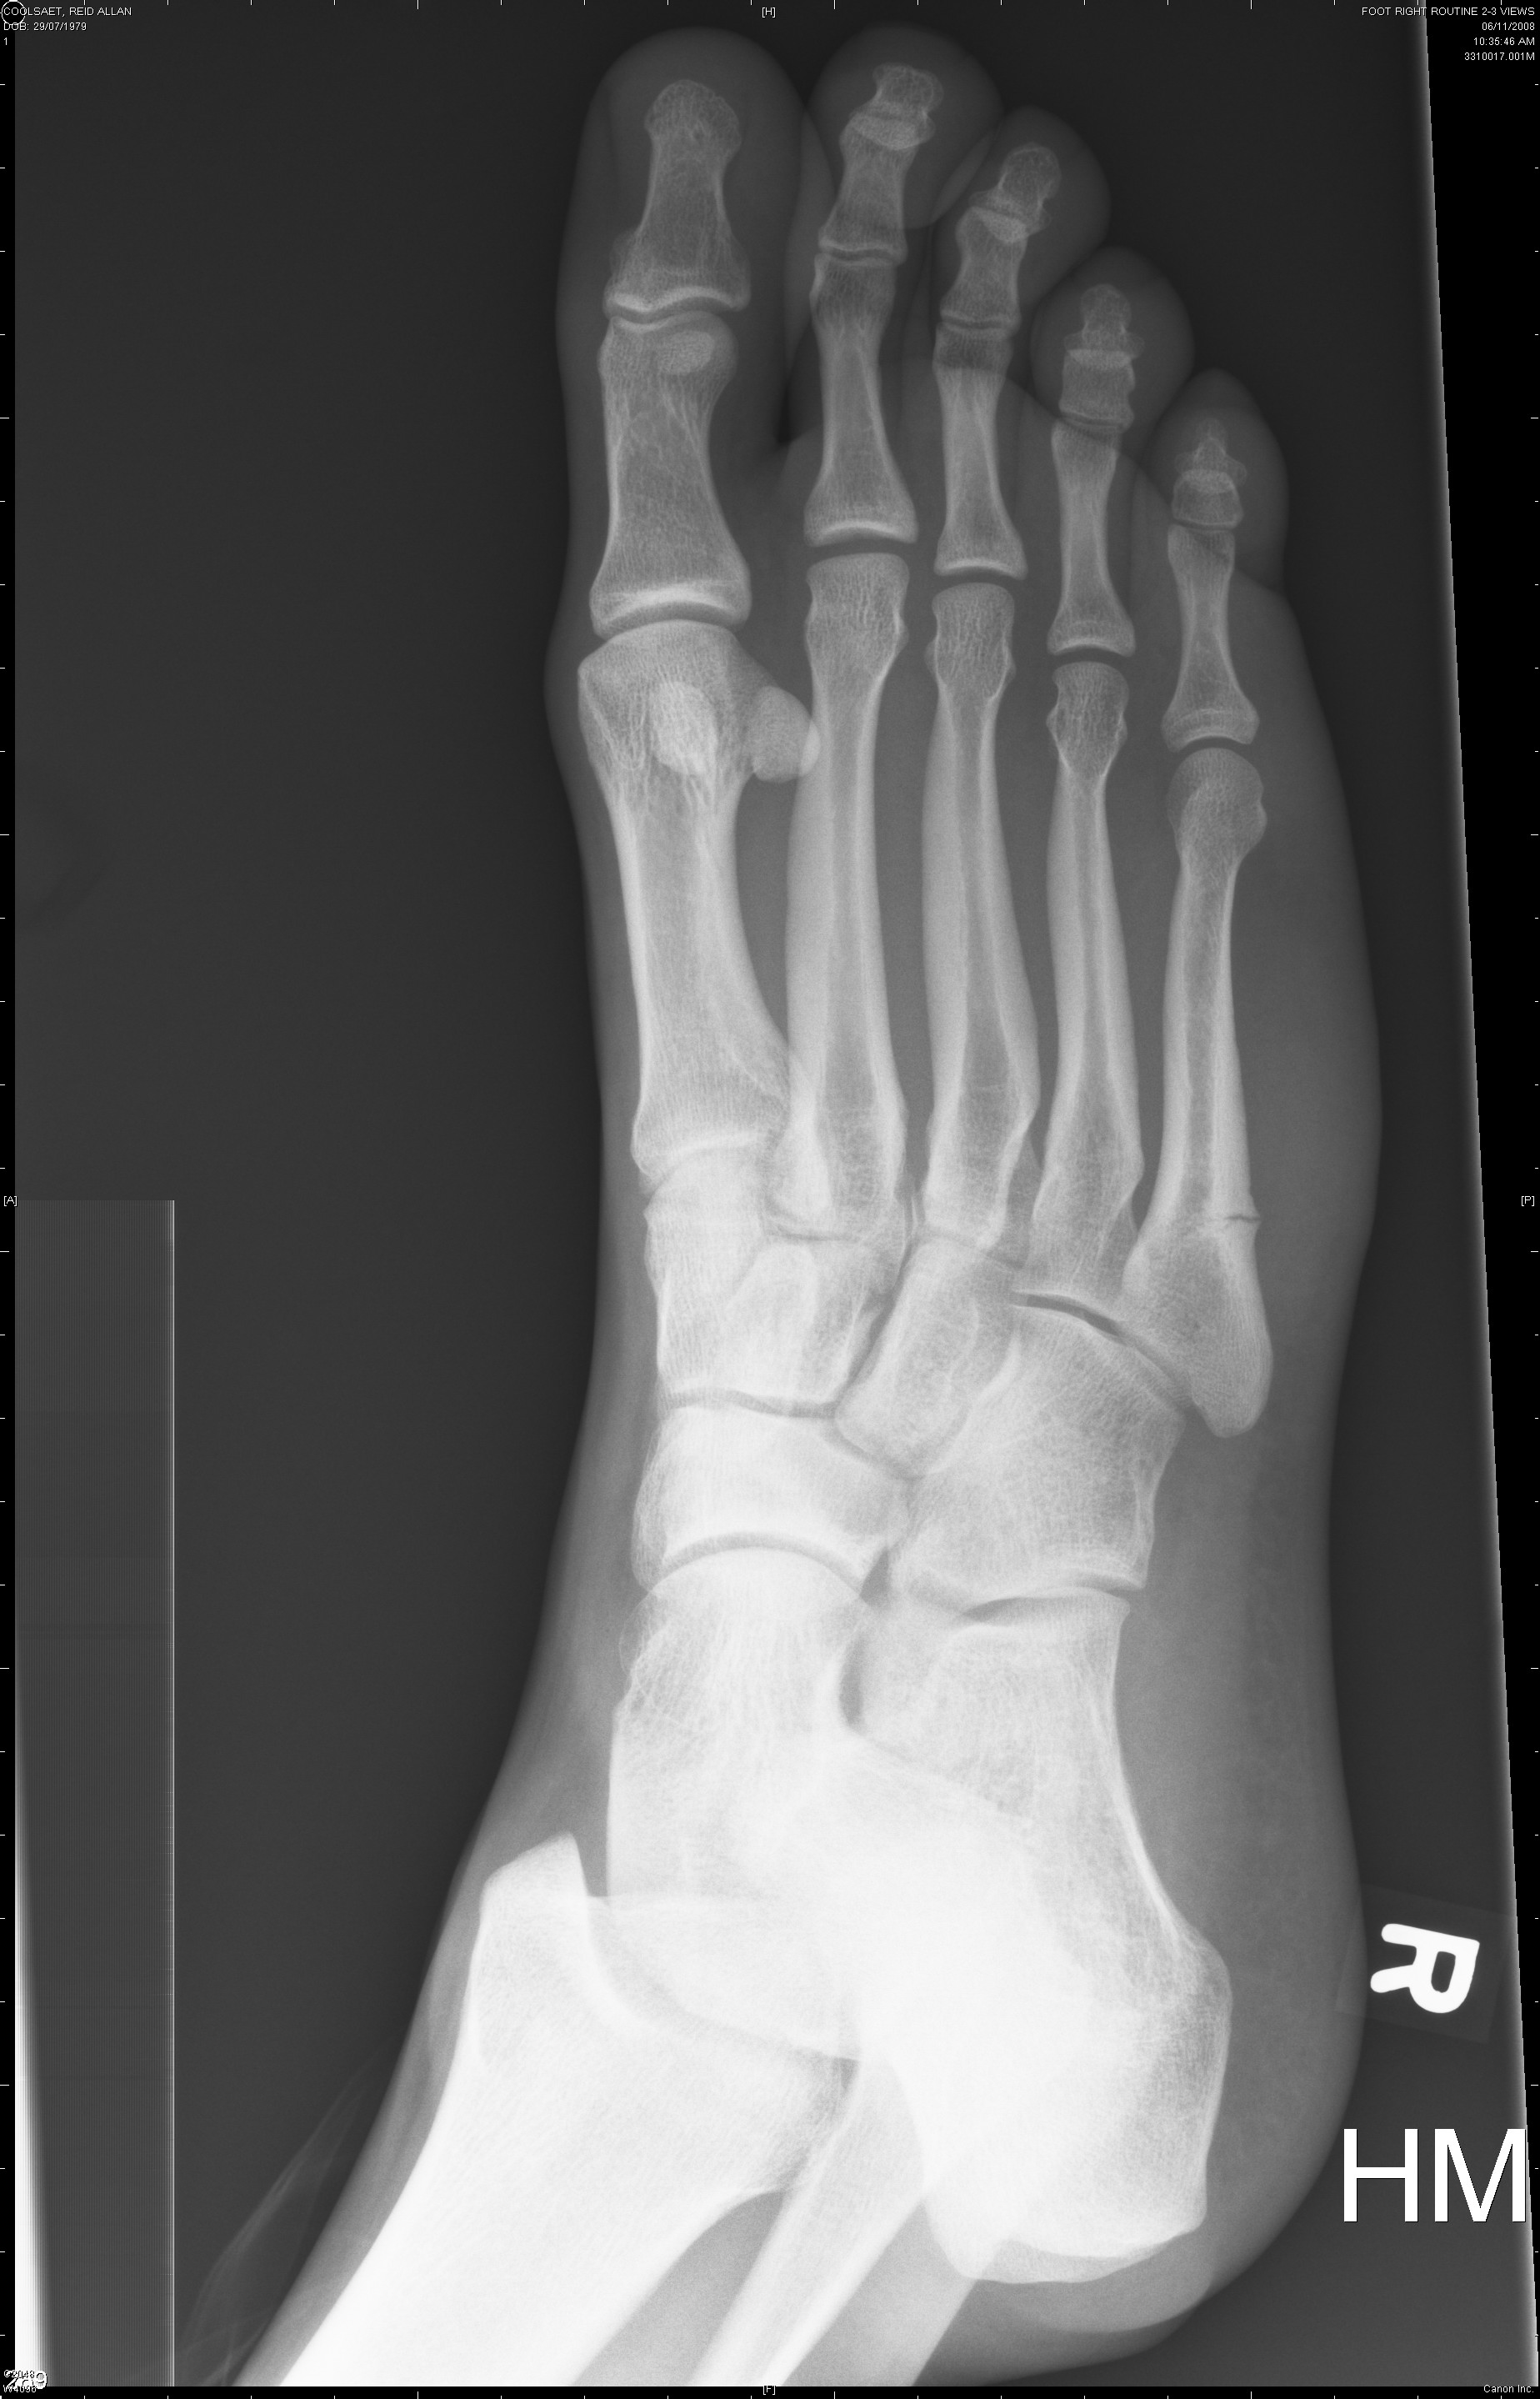

The first two are from November 6th and the last two are from November 22nd.

The fifth metatarsal (long bone on the far right) is broken.